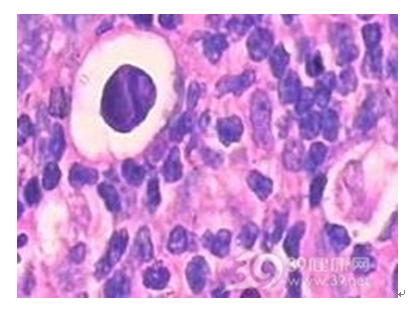

慢性淋巴结炎多继发于头、面、颈部的炎症病灶。淋巴结不同程度的肿大,散见于颈侧区或颌下、颏下区。可略硬但表面光滑,能活动,可有轻度压痛或不适。慢性淋巴结炎本人不需要治疗,检查时应注意寻找原发炎症灶。除颈部各区外还应仔细检查头皮、外耳及口腔、扁桃体、牙龈等隐藏部位。还可按肿大淋巴结的淋巴接纳区找寻原发病灶。

局部淋巴结肿大,最初在常见部位,如:颌下、颏下、颈深上淋巴结肿大、压痛、周界清、活动无粘连。病情继续发展,淋巴结炎症波及周围组织时,淋巴结触诊不活动,疼痛加剧,进一步发展为腺源性蜂窝织炎。

慢性淋巴结炎有反复消胀史,2—3个淋巴结,质中等硬度,活动、压痛。